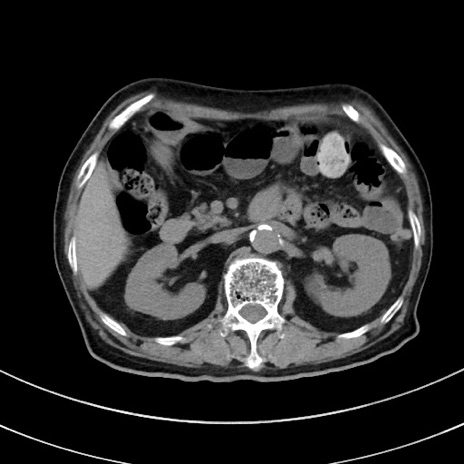

症例33(横断像)

【症例】70歳代 女性

【主訴】心窩部痛

【現病歴】延髄病変の精査・加療にて神経内科入院中。本日より心窩部痛あり。

【身体所見】右下腹部を中心に圧痛と反跳痛あり。

【データ】WBC 10900、CRP 0.02